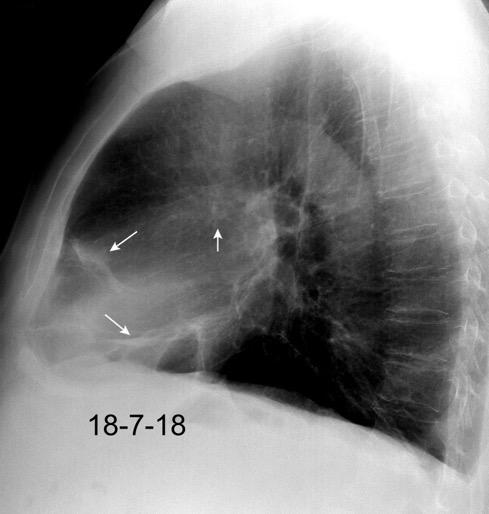

Linfoma de Hodgkin escleroso-nodular

Mediastinitis fibrosa. Fibrosis retroperitoneal.

10-20% de los casos de FM difusa

Reacción a Enf. Autoinmunes. (LED, AR)

Hematopoyesis extramedular

Metersigida / Radioterapia. Enf. inmunoglobulina IgG4. (Riedel, Colangitis, etc.)